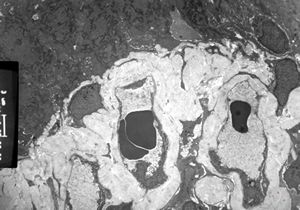

F,79y. | jejunum - amyloidosis